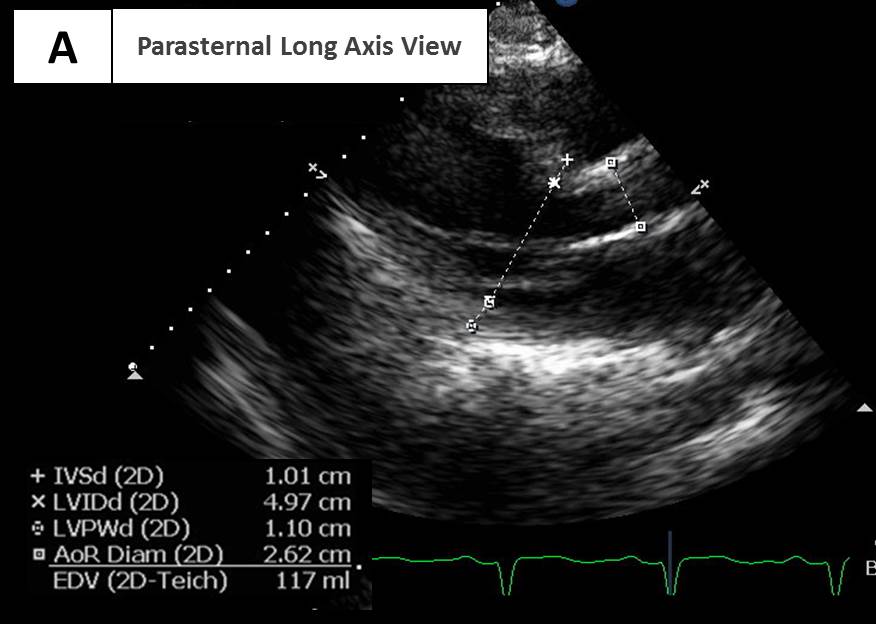

Explanation for Answer A

The presence of a nondilated left ventricle as shown in Video 1 and Figures 1 and 6 indicates that severe AR is acute rather than chronic.